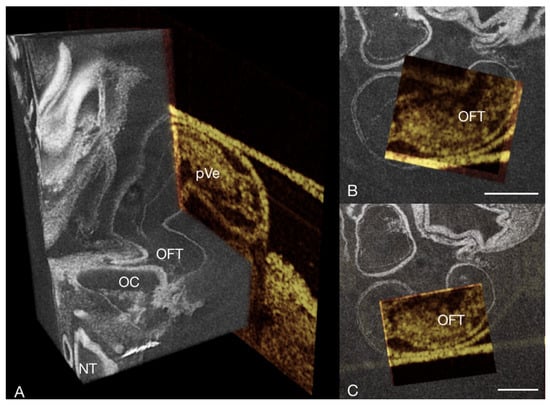

3.2. Image Registration

3.3. Other Findings and Considerations

3.3.2. Using micro-CT for Doppler OCT Based CFD Model Validation